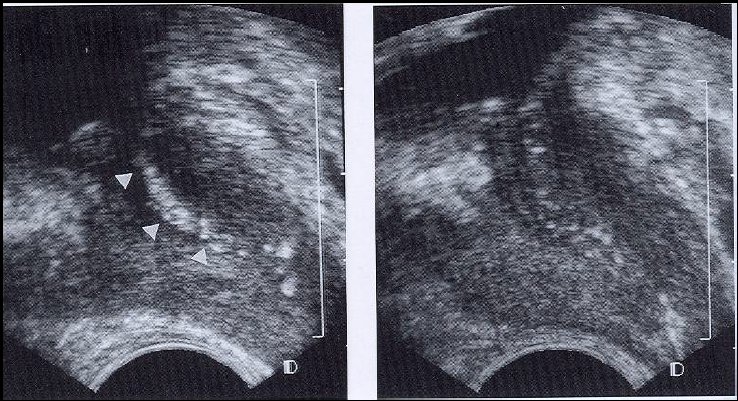

what is this showing? how can you tell?verumon

verumontanum. a trans sonogram of the normal prostate. the “eiffel tower” sign (arrowhead) is seen at the level of teh prostatic utricle.